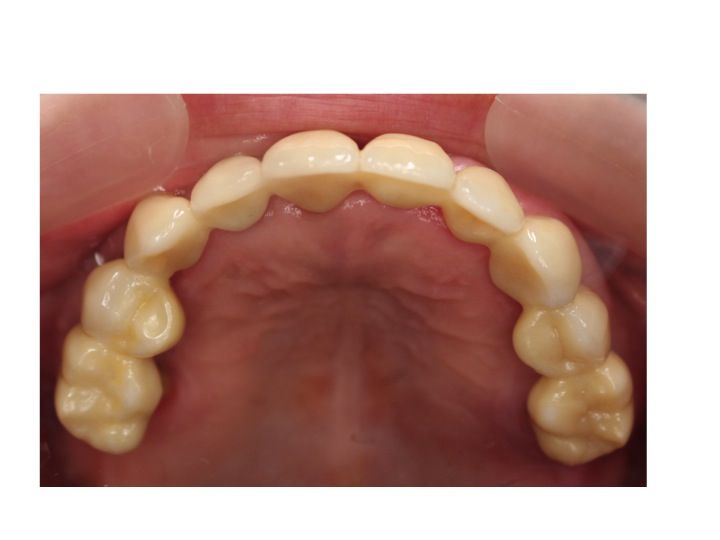

初診時 重度歯周病であり

上顎は全てジルコニアを使用したオールセラミックで

全て固定するタイプで作製してあります。

下顎も

右側奥歯はオールセラミック

左側奥歯はインプラントを使用したオールセラミックとなっています。

上顎の動揺(歯周病で動いている歯)の固定のために

全ての被せ物は連結しています。

完成したジルコニアセラミックを上顎につけたのが以下です。

写真は噛む面(咬合面)から撮影した状態です。